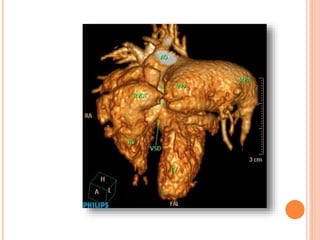

REAL CTA CASES

Absent Pulmonary Valve Syndrome

CASE #1

13 MONTH-OLD BOY

S/P TOF REPAIR

Huge RPA

Huge MPA

Severe PS

Aneurysmal RVOT